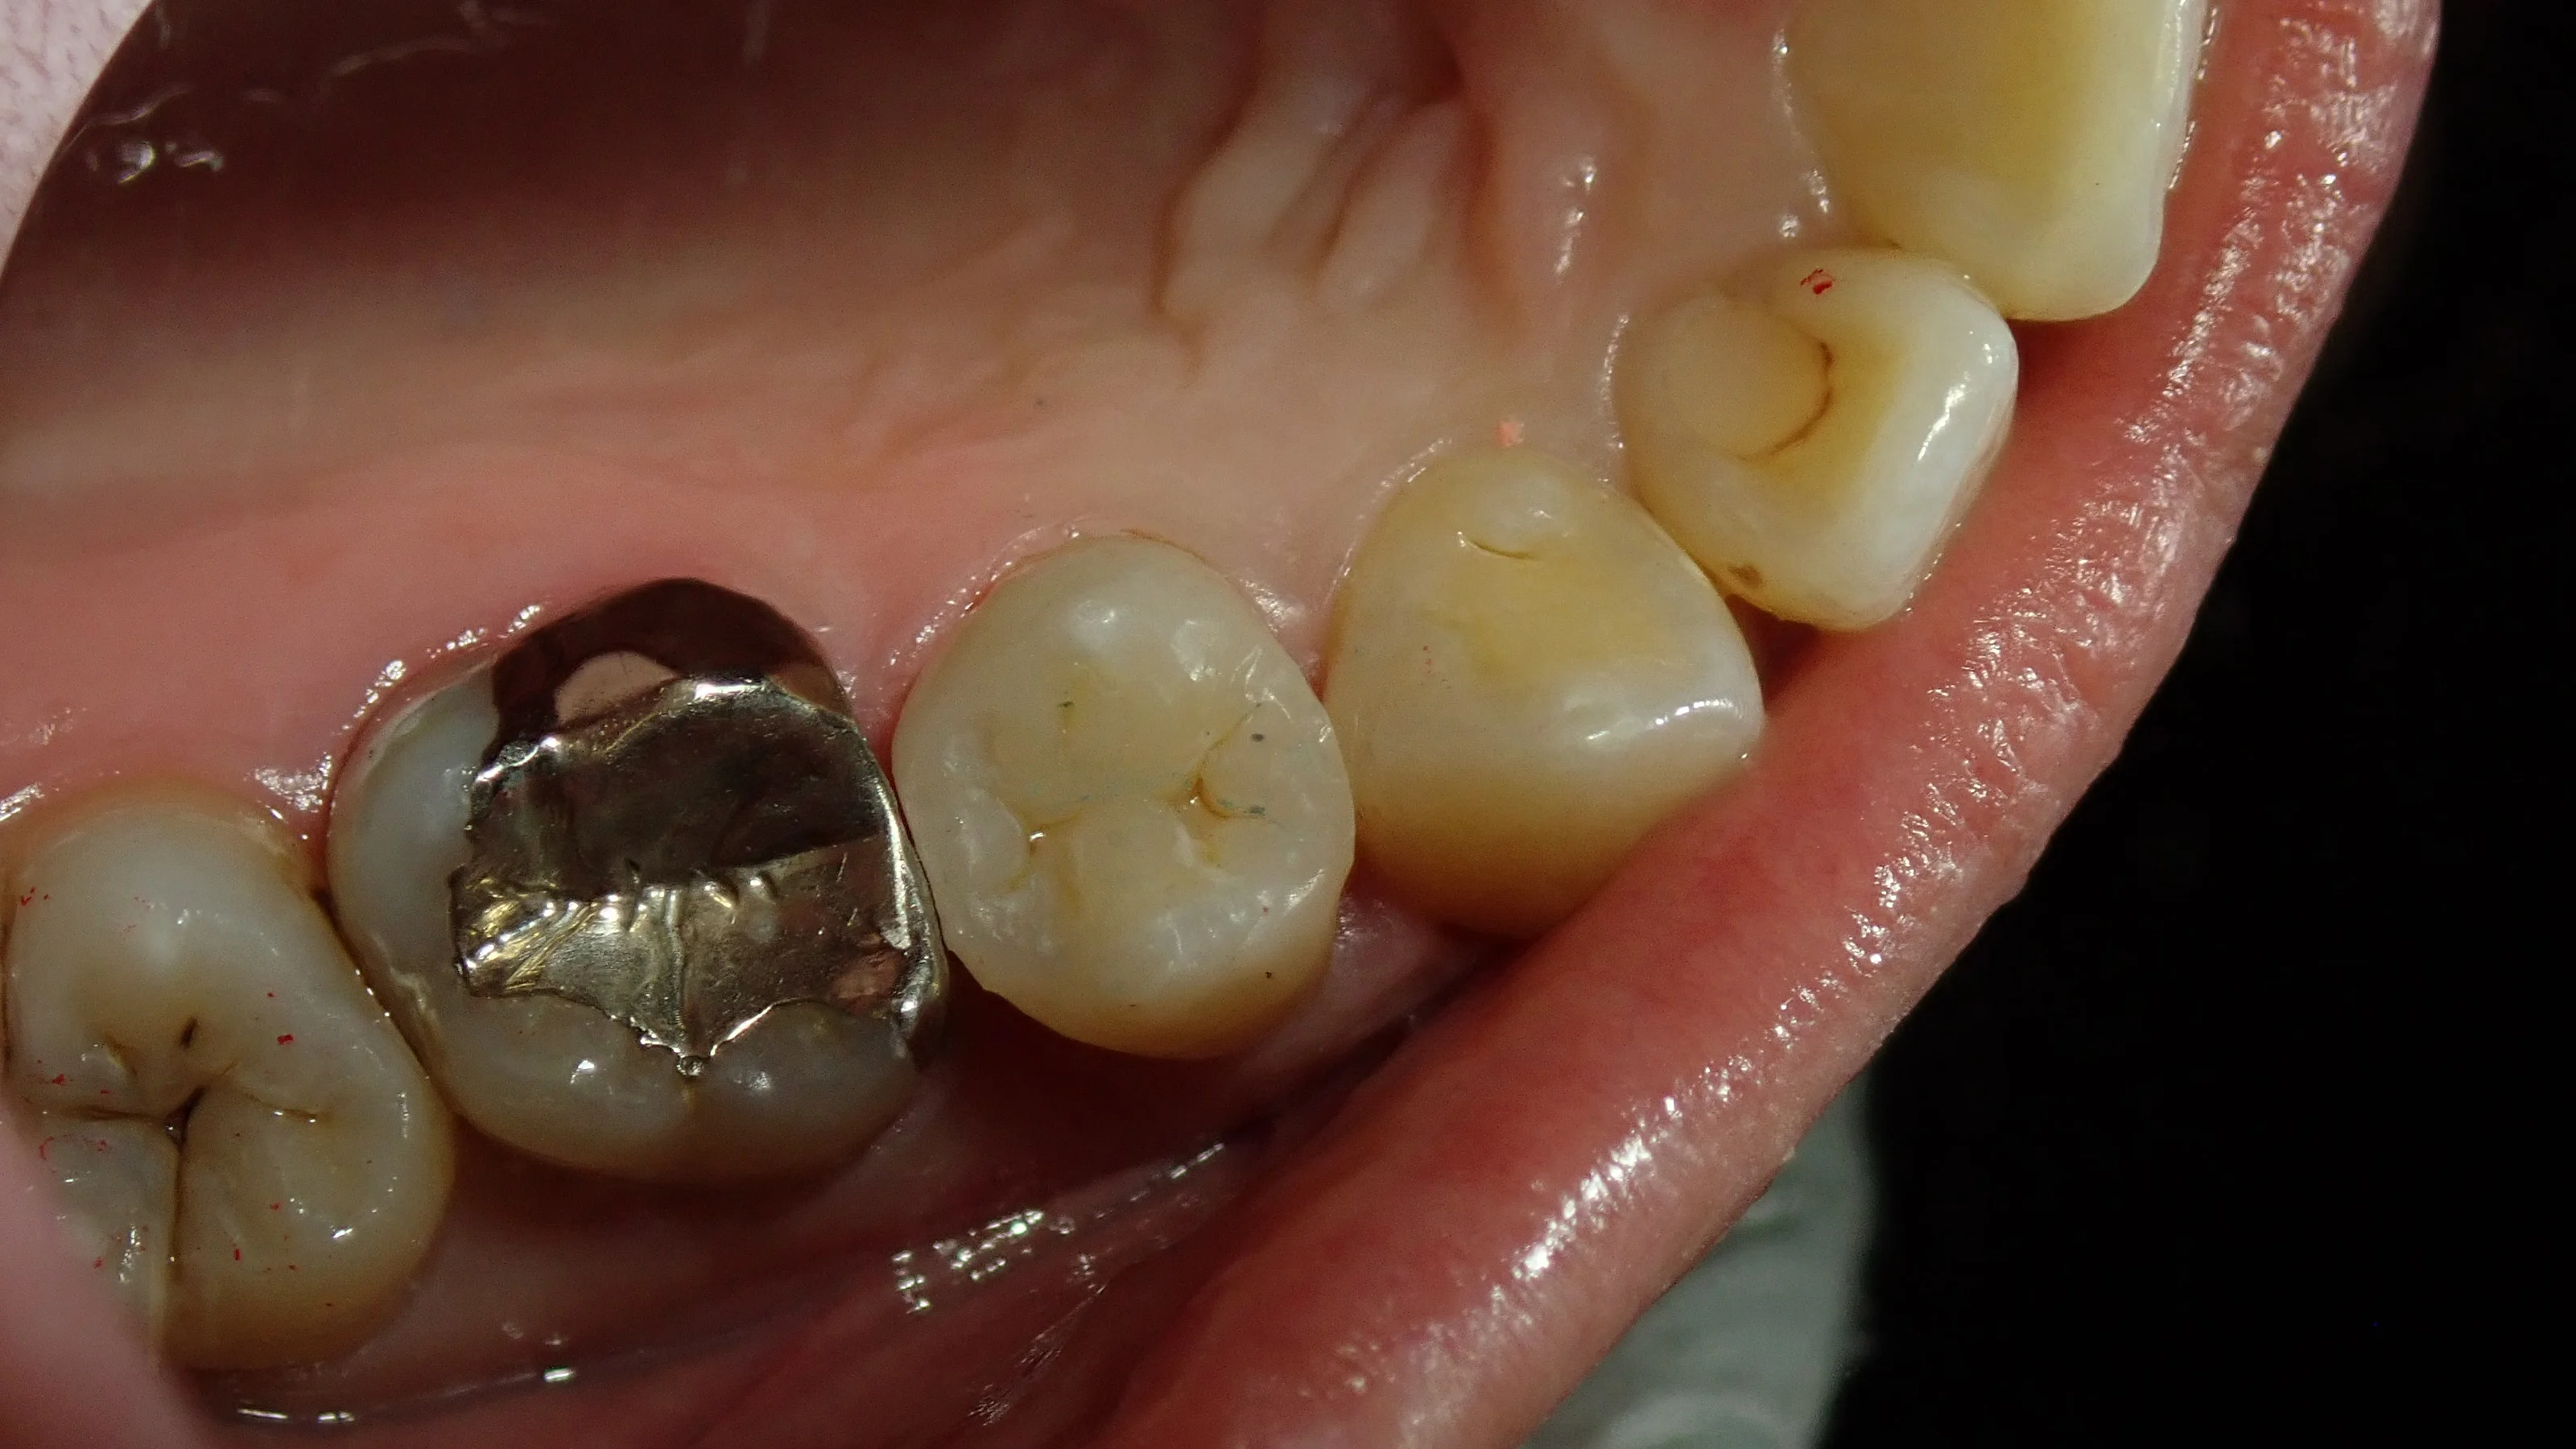

虫歯を取りきったのがこちらです。

最終的な薬には虫歯は到達していなかったので、神経の治療は今回はしないで大丈夫と判断し、詰めていきました。

で、実際に詰め終わったのが、こちらです。

最初にあった隙間が綺麗に埋まっているのが分かるかと思います。

ああいう感じで隙間があると、そこに食べかすが入りやすくなってしまうため、前後の歯との間に虫歯が非常にできやすくなってしまうんですよね。

なので、こんな感じで、歯との間には隙間を作らない方が良いことが多いです。

下手にキツキツにするとそれはそれであまり良くないので、あくまでも、適正な当たり方にする必要がありますけどね。